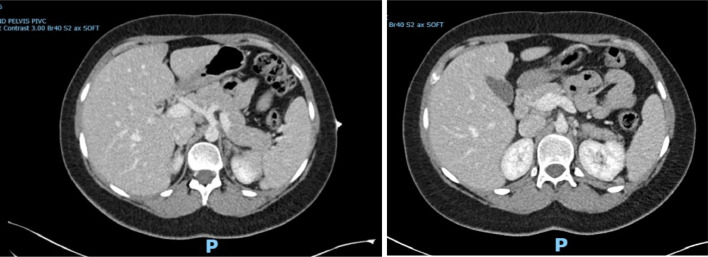

Adrenal haemorrhage in pregnancy is rare but can lead to significant maternal and fetal morbidity if unrecognised. We present the case of a 25-year-old woman in her second pregnancy, who was admitted at 34 + 4 weeks of gestation with severe abdominal pain. Despite initial unremarkable assessments, further imaging revealed a left adrenal haemorrhage, with evidence of prior right adrenal infarction, resulting in primary adrenal insufficiency. Haematological investigations later confirmed heterozygous factor V Leiden as a likely contributing factor. This report underscores the diagnostic challenges of adrenal pathology in pregnancy, where symptoms may overlap with more common conditions. Immediate management with hydrocortisone therapy, supported by a multidisciplinary team (MDT), was employed, with a successful outcome for both mother and child following delivery by caesarean section.

Abstract Image